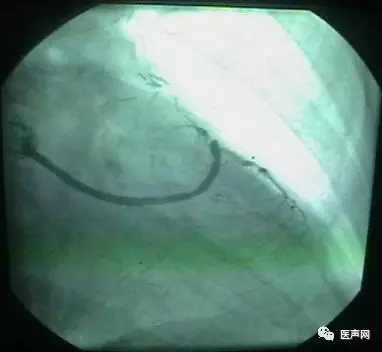

病例2:RCA 支架术后,近端CTO

CAG:RCA 支架术后,近端至远端支架,近端慢性闭塞病变(CTO)(下图所示)

手术经过:AL1.5导引导管,然后换AL2.0导引导管,在微导管支撑下,用硬导丝通过病变,直径1.25mm球囊至远端,远端有夹层,重至真腔,

但近端不确定是否真 腔,2.0mm CTO球囊可至RCA中段,导引导管弹出,重新进入,但近端可能是假 腔,终止手术,下次再试。

近端导丝在支架轮廓外侧

有3个Mark标记者为微导管,微导管可达RCA远段,但不一定在支架内走行。

· 导引导丝虽然在支架网眼外穿行,但球囊可以无阻力穿过,这不一定是真腔。导丝可能走在支架网眼与管壁之间,球囊不能扩!

· 即使导丝穿出支架网眼,但球囊可以无阻力穿过网眼。扩张时一定慎重!

· 做CTO时导丝可能从真腔-假腔-再到真腔。